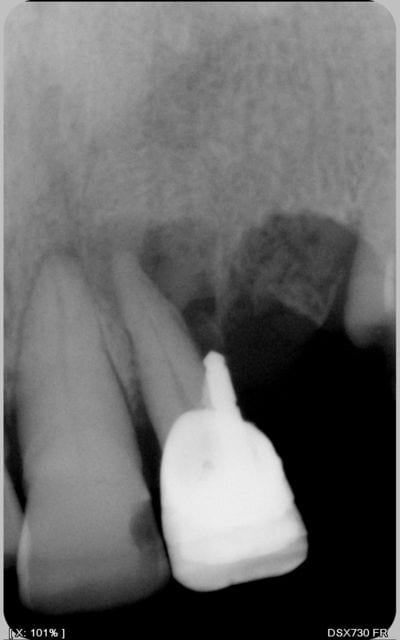

tenez ! cadeau

c'est le même praticien

vous noterez la position du pivot

et l'optimisme du praticien qui l'a posé dans une dent vivante

"coup de chance" ou "manque de pot" c'est à coté

je ne sais ce qui valait mieux

Charly est à gauche , donc . gtout compris.com:)